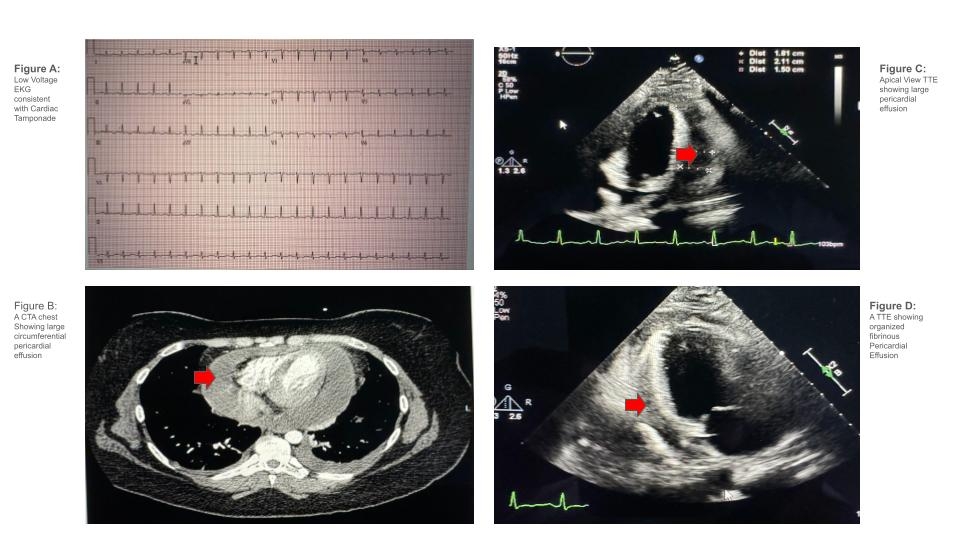

When a Cutie Takes Your Breath Away: A Case of Cutibacterium Acne-induced Pericardial Effusion

A 29-year-old female with type II diabetes and hypothyroidism presented with a week of shortness of breath, chest pain, lightheadedness, and loss of consciousness. Workup showed WBC (20.6), CRP (283), and ESR (85). Echocardiogram revealed a large pericardial effusion with right ventricular collapse, indicating cardiac tamponade. She underwent pericardiocentesis, draining 400 ml of exudative fluid. Unfortunately, the effusion rapidly re-accumulated, requiring a pericardial window procedure with drainage of fibrinous, loculated fluid over 2 days, improving her symptoms. She was discharged on colchicine and NSAIDs, however she returned 5 days later with recurrent symptoms and fever. The culture of the previous fluid showed Cutibacterium acne. Histopathology of pericardial biopsy revealed fibrinoid pericarditis. She was treated with ceftriaxone, and transitioned to doxycycline for 14 days, along with 14 days of ibuprofen and 3 months of colchicine. At 3-month follow-up, she was asymptomatic with no effusion recurrence.